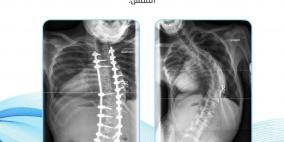

المهندس سليم مسلم يبتكر جهازا ثوريا لعلاج العمود الفقري

خاص| بالفيديو: أسباب تشوهات العمود الفقري وطرق الوقاية والعلاج